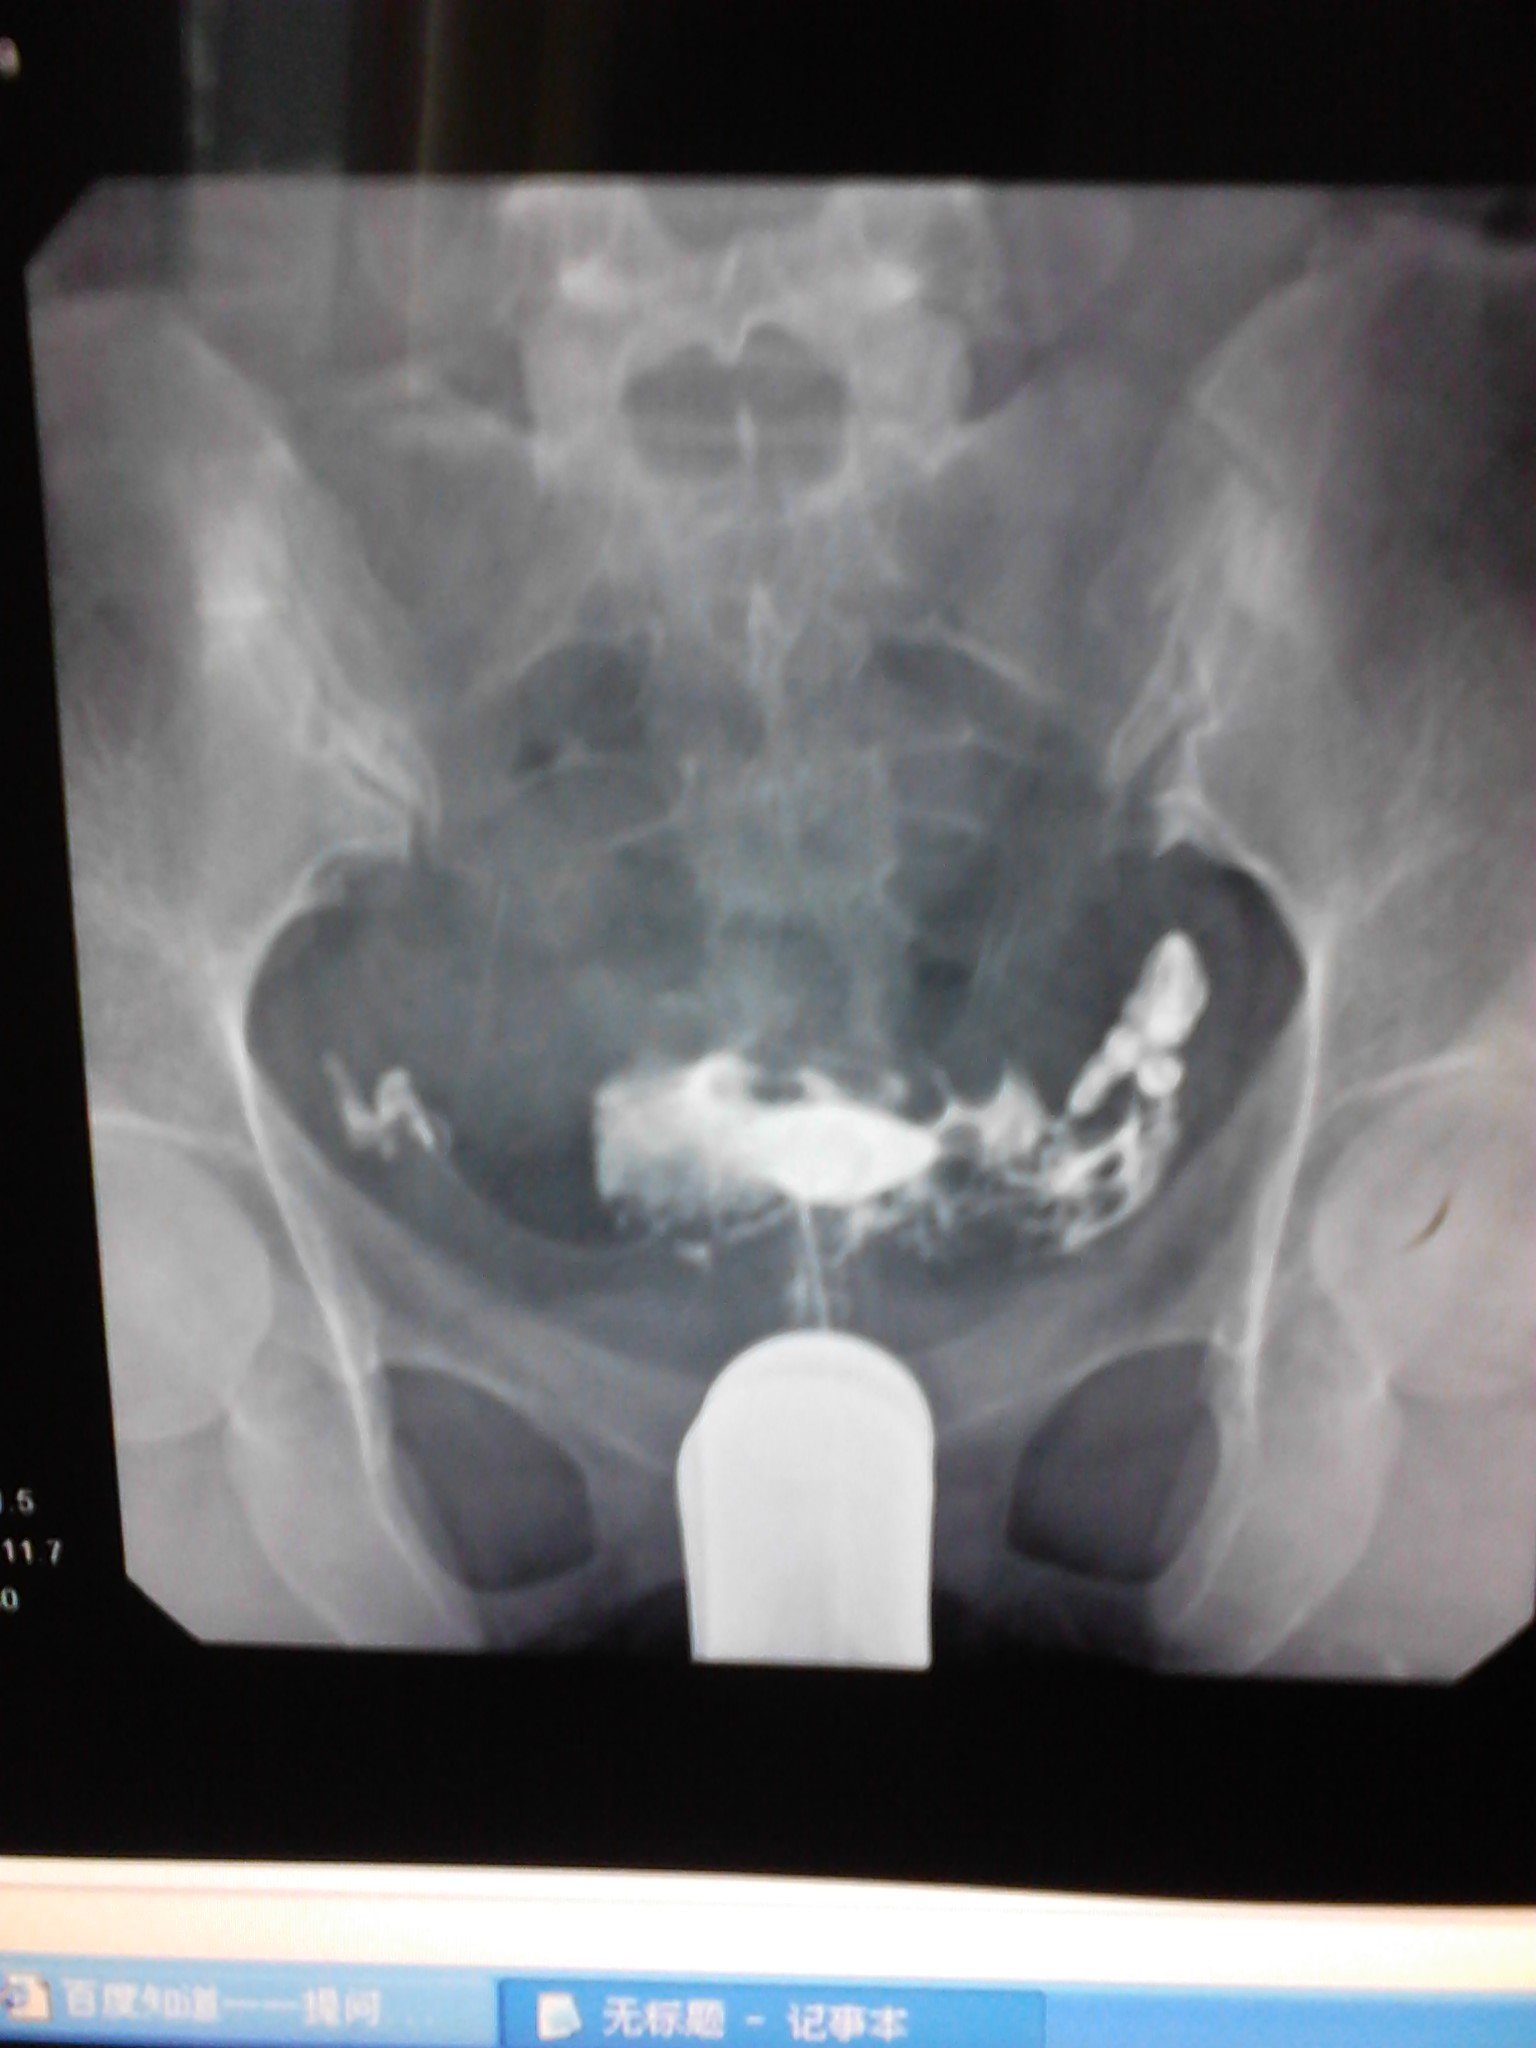

请大家看看造影的报告单,,,还有怀孕的机会吗? 患者信息:女 25岁 贵州 遵义 病情描述(发病时间、主要症状等):子宫腔大小.形态无明显异常.子宫粘膜面光滑整齐.宫腔内见气囊及气泡所致充盈缺损。双侧输卵管全程显影.双壶腹部粘膜皱襞增粗.双侧伞端呈锥状.其内造影剂呈喷射状进入腹腔.进入腹腔之造影剂弥散欠佳曾经治疗情况及是否有过敏、 遗传病 史:现在正在吃中药 点击展开 宇文令秋_1EAj 2012-06-17 13:32 满意回答 帮顶。。。。。。。。。。。。 欧阳弘新_SmTk 2012-06-17 13:51 宝宝知道提示您:回答为网友贡献,仅供参考。 相关问题 医生看看我的造影报告单 数字化X造影检查报告单还能生育吗? 做完造影这样的结果,次月跟第三个月会怀孕吗

患者信息:女 25岁 贵州 遵义 病情描述(发病时间、主要症状等):子宫腔大小.形态无明显异常.子宫粘膜面光滑整齐.宫腔内见气囊及气泡所致充盈缺损。双侧输卵管全程显影.双壶腹部粘膜皱襞增粗.双侧伞端呈锥状.其内造影剂呈喷射状进入腹腔.进入腹腔之造影剂弥散欠佳曾经治疗情况及是否有过敏、 遗传病 史:现在正在吃中药